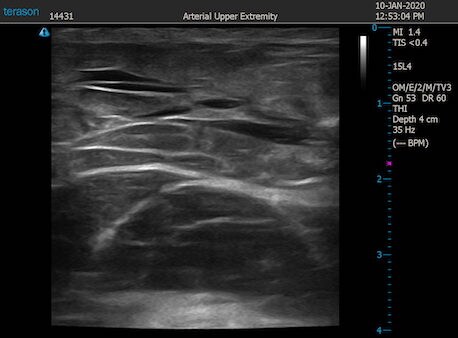

いつものように3Dタッチビュー(超音波)で

皮下脂肪層を評価してみましょう。

右二の腕